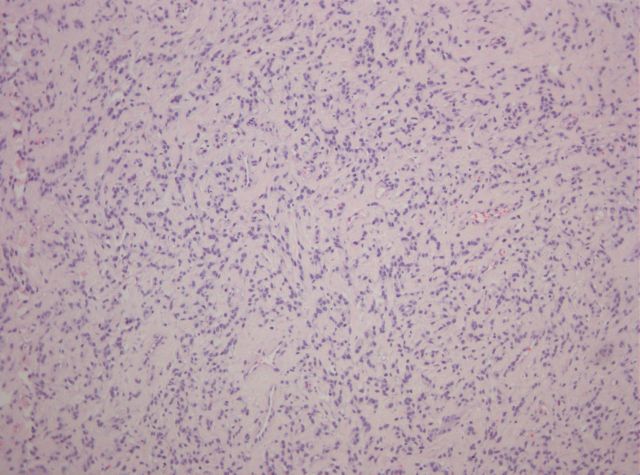

Hematoxilina-Eosina x100 -

Abundantes estructuras capilares de paredes finas y delicadas.

Hematoxilina-Eosina x200 -

Proliferación mesenquimal, sin rasgos citológicos de atipia celular; matriz estromal fibroconjuntiva.